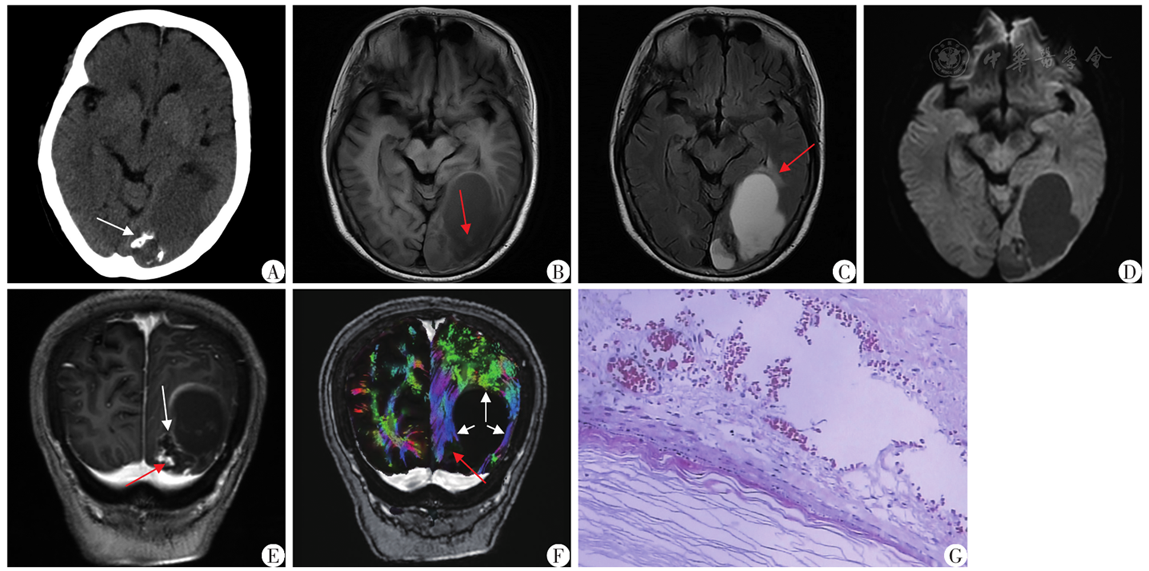

图2 左侧枕叶表皮样囊肿患者术前影像及术后病理资料A:CT以稍低密度为主,CT值26.5 HU,边缘少许钙化(白色箭头所示);B:MRI T1WI呈稍低信号,伴内部少许片絮状等信号(红色箭头所示);C:FLAIR信号不均匀减低、灶周局部脑水肿(红色箭头所示);D:DWI无弥散受限;E:边缘环形强化及疑似壁结节明显强化(红色箭头所示),交界区脑实质虫蚀样破坏/尖角状突起(白色箭头所示);F:DTI示病变周围白质纤维束受压推压(白色箭头所示)、部分中断(红色箭头所示);G:病理示囊壁复层鳞状上皮及囊内角化物(HE染色,×200)

Fig.2 Preoperative imaging and postoperative pathological data of patient with an epidermal cyst in the left occipital